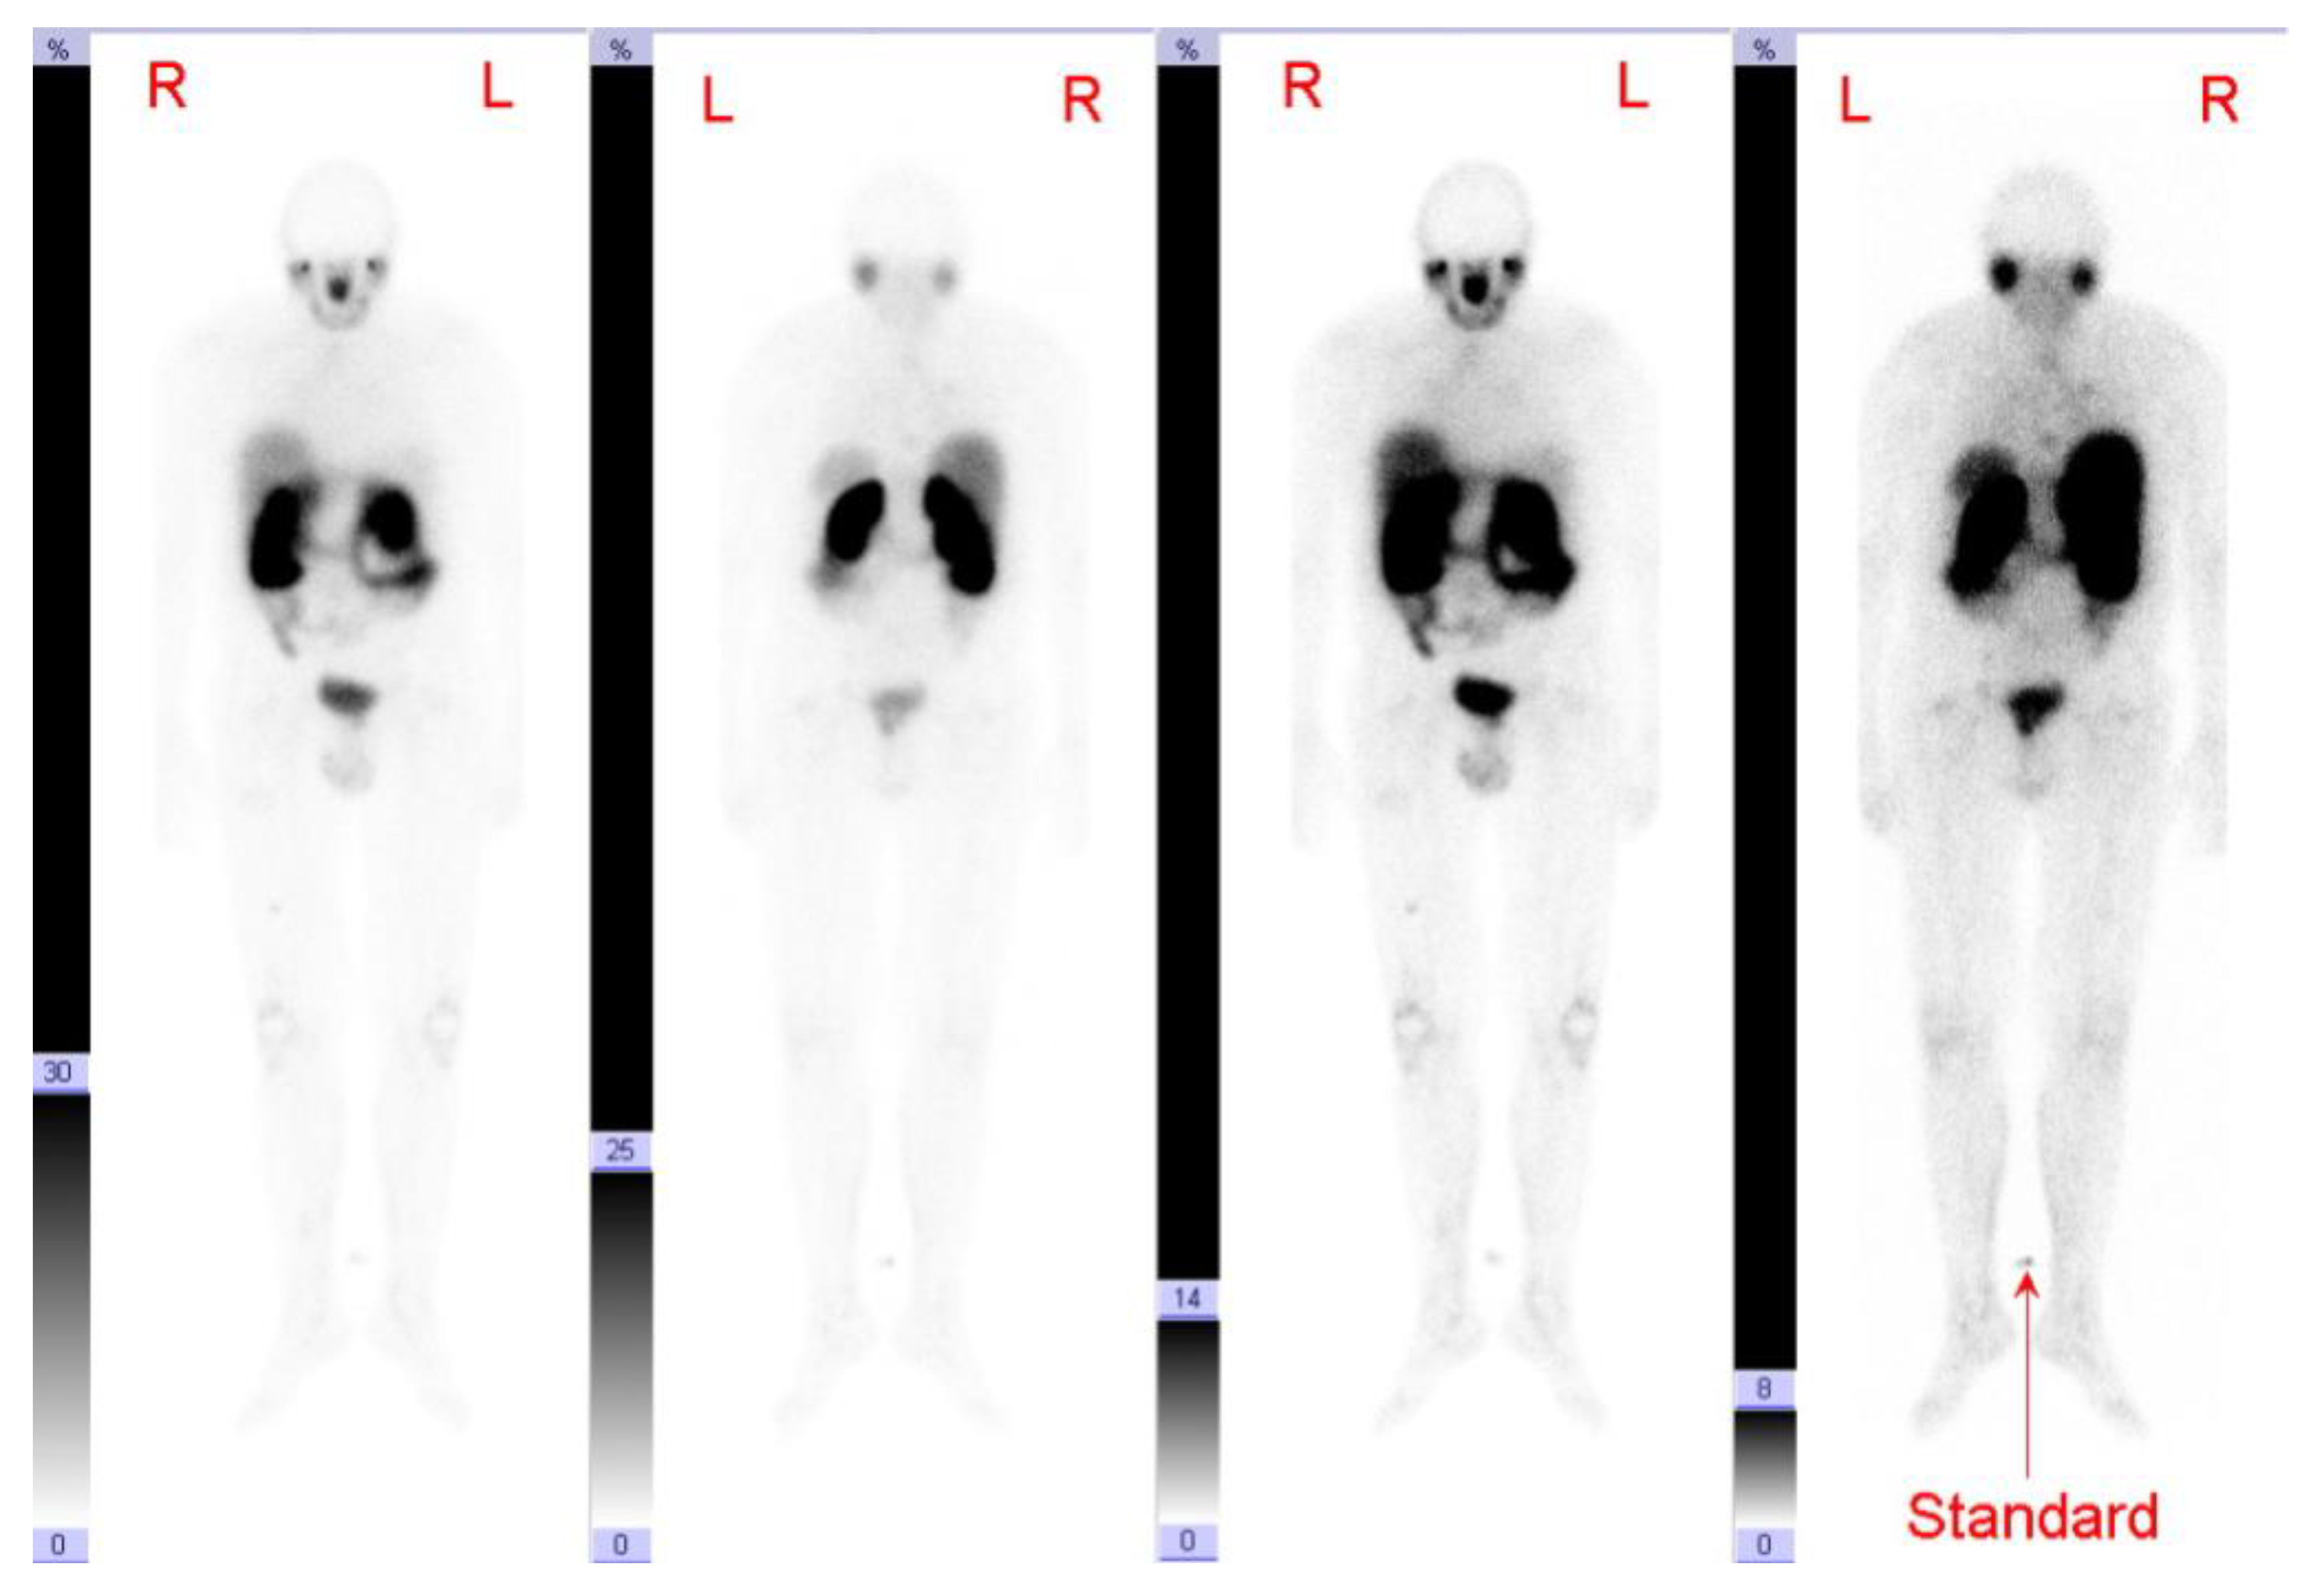

3.2. 68Ga-PSMA-PET/CT

3.4. Imaging Findings

| Patient | 18FDG-PET/CT and 68Ga-PSMA-PET/CT Results | PSMA Expression | ||||||

|---|---|---|---|---|---|---|---|---|

| Diagnosis of Primary Tumor | Year of Scan | Interval between 18FDG-PET/CT and 68Ga-PSMA- PET/CT (Days) | Tumor/Metastases Locations Number of Lesions (N) Median Size, cm (Range) | FDG- PET/CT Median SUVmax (Range) | PSMA- PET/CT Median SUVmax (Range) | Tumor Samples | Extend of PSMA- Expression | |

| Disease Location | 68Ga-PSMA- PET/CT Median SUVmax (Range) * | Clearly (Discreet) PSMA-Positive Lesions/ Total Rated Lesions | 18FDG-PET/CT Median SUVmax (Range) * | Clearly (Discreet) FDG-Positive Lesions/ Total Rated Lesions 1 | Number of Clearly Dis-Cordant Lesions 2/Total Rated Lesions 1 | Description of Clearly Discordant Lesions 1 |

|---|---|---|---|---|---|---|

| ATC | ||||||

| Mediastinal lymph node | 3.3 | 0 (1)/1 | 2.7 | 0 (1)/1 | 0/1 | - |

| Pulmonary metastases | 1.3 (0.6–4) | 0 (0)/9 | 5.0 (1.5–28.3) | 9 (0)/9 | 9/9 | 9 FDG+, PSMA− |

| Local tumor recurrence/ thyroid bed lesions | 2.5 | 0 (0)/1 | 16.3 | 1 (0)/1 | 1/1 | 1 FDG+, PSMA− |

| PDTC | ||||||

| Osseous metastases | 3.85 (1.8–9.0) | 2 (3)/10 | 9.9 (1.2–31.2) | 6 (0)/10 | 7/10 3 | 2 PSMA+, FDG− 5 FDG+, PSMA- |

| Cervical lymph nodes | 5.75 (4.1–7.4) | 0 (1)/2 | 40.25 (32.1–48.4) | 2 (0)/2 | 1/2 4 | 1 FDG+, PSMA− |

| Mediastinal lymph nodes | 6.0 (2.1–10.1) | 1 (1)/4 | 30.85 (5.6–55.9) | 4 (0)/4 | 2/4 5 | 2 FDG+, PSMA− |

| Pulmonary metastases | 3.45 (2.0–6.3) | 0 (0)/15 | 15.5 (6.6–51.5) | 15 (0)/15 | 15/15 | 15 FDG+, PSMA− |

| Local tumor recurrence/thyroid bed lesions | 3.3 (2.4–4.2) | 0 (0)/2 | 43.5 (19.1–67.9) | 2 (0)/2 | 2/2 | 2 FDG+, PSMA− |

| Cerebral metastases | 12.3 | 1 (0)/1 | 31.4 | 1 (0)/1 | 0/1 | - |

| Soft tissue/others (inguinal lymph node metastasis) | 5.25 (4.3–6.2) | 0 (1)/2 | 33.1 (31–35.2) | 2 (0)/2 | 1/2 4 | 1 FDG+, PSMA− |